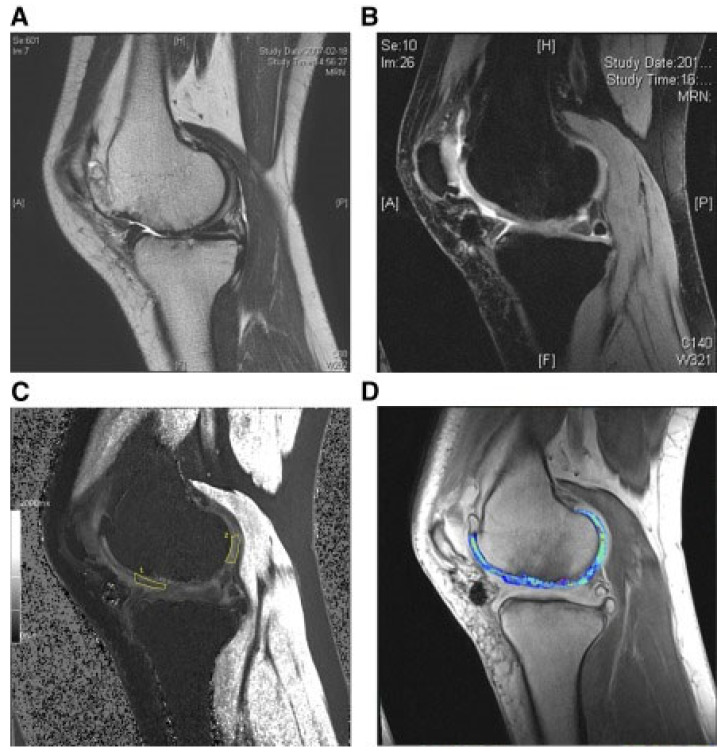

還評估了人臍帶血來源的間充質干細胞(HUCB-MSC)治療軟骨再生的安全性和有效性。根據國際軟骨修復協會的數據,HUCB-MSC用于治療7名患有KLIII級OA和IV級軟骨缺損的患者。同種異體HUCB-MSC在體外生長,然后與HA水凝膠結合并應用于損傷部位。微骨折方案與這些細胞結合使用。12周后,修復的組織似乎成熟,24周后,臨床評分增加。在整個7年隨訪過程中,臨床改善的穩定性也值得注意。組織學用于在手術后一年顯示透明軟骨,而MRI用于在手術后3年顯示軟骨再生,如圖所示圖3(其中釓-DTPA用作造影劑,以藍色顯示)。

圖3:HUCB-MSC治療后3年軟骨再生的MRI評估

(A) 術前軟骨缺損。(B) 移植后3年軟骨再生。(C) 通過在標記區域采樣來計算相對軟骨松弛率的變化。(D) 顯示與藍色信號相關的GAG含量增加。